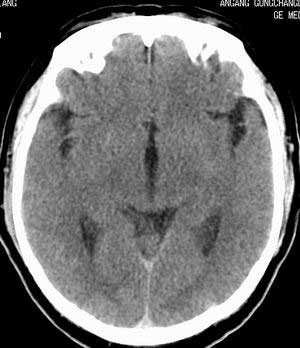

脑实质密度均匀,未见异常密度灶,脑沟裂池室形态大小正常,中线结构居中.

正常头颅ct表现

正常颅脑ct

正常颅脑ct片。

颅内未见异常,属正常头颅ct表现,建议薄层扫描内耳。